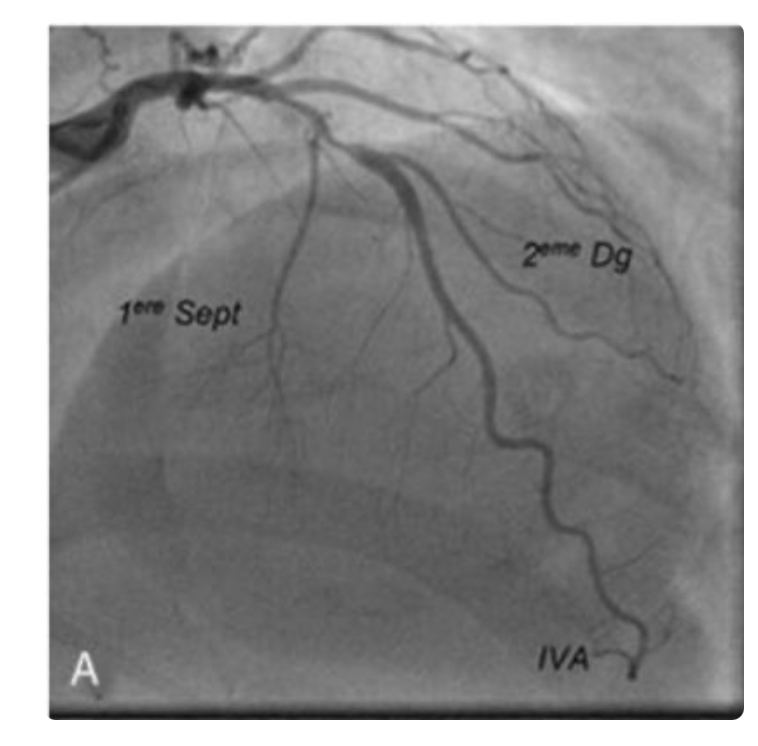

A propos de cet examen : (cf photo)

A B